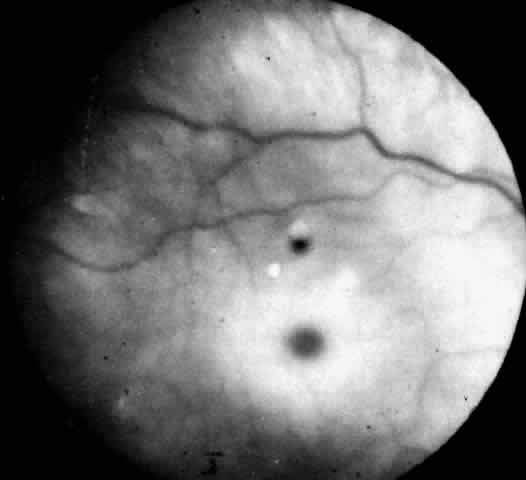

Recognition of the cherry-red spot at the macula is a major diagnostic criterion of Tay-Sachs disease (Fig. 3). It is caused by the accumulation of intracytoplasmic membranous bodies in retinal ganglion cells.

Fig. 3. Fundus of an 18-month-old boy with Tay-Sachs disease. Note cherry-red spot and small white parafoveal halo.

The circular appearance of the fundoscopic lesion reflects the anatomy of the macula. No ganglion cells are present at the very center of the macular region, the foveola, and the central red spot simply represents the normal choroidal background color. The ganglion cell layer surrounding the foveola is several cells thick, and loading of these neurons by storage products results in loss of retinal transparency and a white parafoveal halo. Peripheral to the macular region the ganglion cell layer is only one cell thick, and lipid accumulation in these cells is, therefore, less conspicuous.

Tay-Sachs disease is also the most common storage disease causing macular cherry-red spots (Table 2).3 The variation in the shade of the red spot reflects racial fundus pigmentation. The halo is opaque, slightly elevated, and 1.5 disc diameters in width. The outer border is less sharp than the inner border.